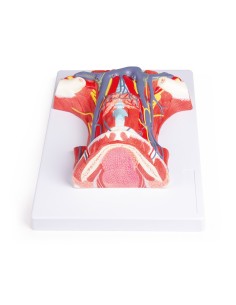

Découvrez le monde de l'anatomie avec des modèles anatomiques de précision

Bienvenue sur Tuttoanatomia.it, le portail de référence en Italie pour l'achat de modèles anatomiques, de posters, de lits portables, de simulateurs médicaux et de littérature spécialisée. Grâce à nos modèles anatomiques de pointe de 3B Scientific et Erler Zimmer, nous offrons une expérience d'apprentissage inégalée.

Des modèles anatomiques détaillés pour tous les besoins

Du crâne en 22 parties à verrouillage magnétique aux modèles de colonne vertébrale, des modèles d'articulation aux modèles de cœur, chaque pièce de notre collection est conçue pour une immersion totale dans l'étude de l'anatomie humaine. Nos modèles, réalisés à partir de scans d'os réels, garantissent une expérience tactile authentique et une fidélité de poids presque identique aux originaux.

Des outils pédagogiques innovants pour l'enseignement et la pratique de la médecine

Indispensables aux étudiants comme aux professionnels, nos modèles anatomiques sont des outils pédagogiques qui permettent d'observer les structures anatomiques avec précision, en évitant les dissections ou les études invasives. Ils sont également utiles pour expliquer les pathologies aux patients, ce qui rend la communication plus efficace et permet de gagner un temps précieux.